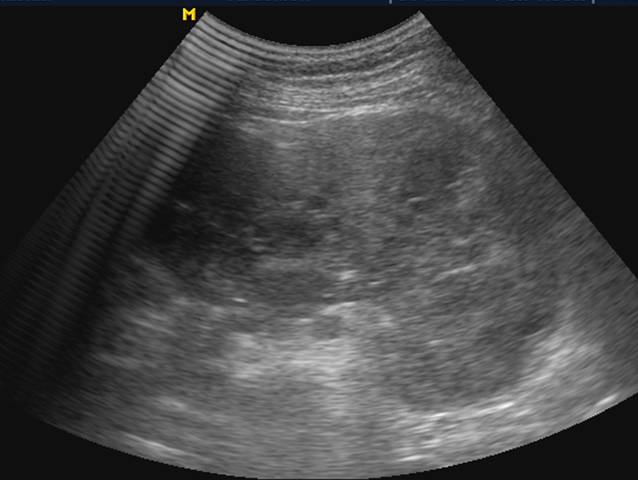

单纯性脾囊肿: